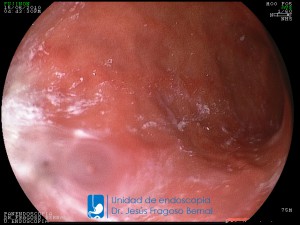

La Unidad de Endoscopía fue creada en 2002 por el Dr. Jesús Fragoso Bernal, es pionera en el estado por la utilización de la tecnología más avanzada, que nos permite ofrecer servicios integrales de diagnóstico y tratamiento para las enfermedades del aparato digestivo.